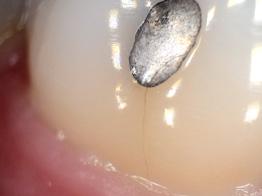

by Larry M. Guzzardo

The process of moving a patient from one member of the team to another is called a “hand-off.” We do this by never leaving a patient alone without letting them know who and what to expect next. It means you never leave them alone in a treatment room, wondering who’ll come in next or how long they will be there, or you never drop them off at the front desk to talk to a receptionist on the phone. It requires informing your patient of each step of the way by explaining who and what comes next, anticipating their needs, and introducing them to the next team member, all while creating an environment that will increase treatment acceptance and reduce canceled and broken appointments.

That’s why I propose that the patient experience multiple hand-offs throughout their visits. Consider how many times this can happen. The patient needs to be handed off by the dentist to his or her dental assistant. The dental assistant then needs to hand-off the patient perfectly to the front office person, who then also needs to clear everything up with the patient again.

The hand-off that helps a patient connect:

Of course, in each hand-off, the patient must be included. Every time a patient hears the information passed on in the hand-off, a little more sinks into their mind. I find that dental office hand-offs are not long enough and do not involve enough people. This brevity is what creates confusion for the patient. How often do we see that the front-desk hand-offs can be so brief they’re almost curt? For example, “We need a 30-minute appointment for a DO on 17.”

And sadly, I often hear this in clinical areas as well. The dentist will simply tell their assistant what is needed next without including the patient in the exchange. So, now we have a patient with little or no commitment to their treatment. There are no “dots” to connect yet; it

only takes a few seconds more to explain the next step.

This is what should happen to help patients “connect the dots”: The dentist should be communicating with the patient throughout the appointment about what they are doing, why they are doing it, and how things are progressing. At the end of the appointment, as the chair is brought up, the dentist must take command by coming around to the front of the chair, connect with the patient by making eye-to-eye contact, and take the following 10 steps: